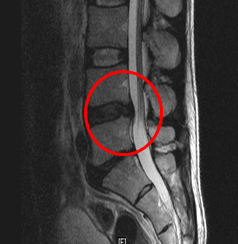

요추 추간판 수핵탈출증의 단계

팽륜

돌출

탈출

전위